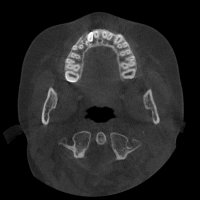

La Tomografia Computerizzata Cone Beam è stata adottata nel nostro studio per l'imaging diagnostico 3D nel 2010.

Non viene utilizzata di routine ma solo in casi complessi seguendo sempre il principio ALARA (As Low As Reasonably Achievable=Esposizione alle radiazioni X il più basso possibile in accordo alle esigenze diagnostiche e terapeutiche).

Nella routine, la stessa apparecchiatura consente la presa di immagini digitali 2D a basso livello di esposizione radiologica.